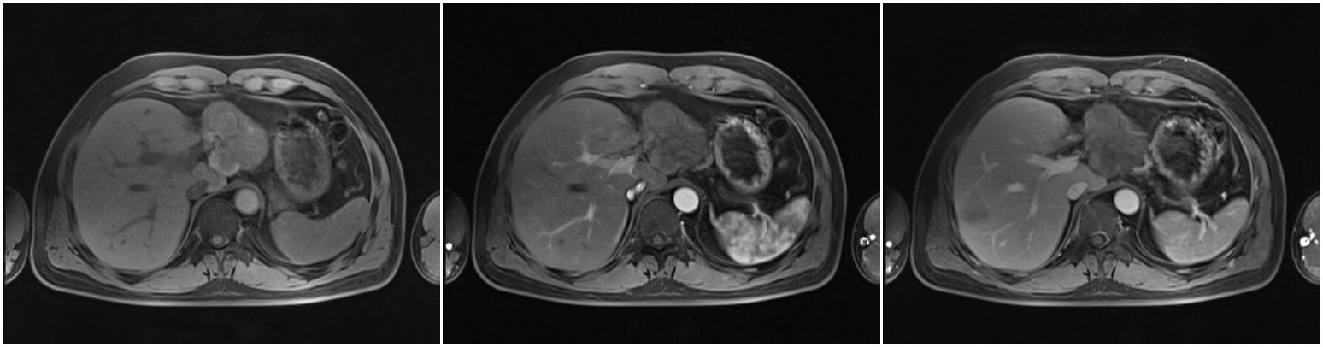

2011-06-09(第二次TACE后4个月)复查肝脏CT示:肝左叶病灶继续缩小,但仍有肿瘤残留。AFP:8137 ng/ml(较上次复查明显升高)。

2011-06-14行第3次TACE术(碘化油15ml,THP 35mg)

2011-08-15复查CT示:肝左叶病灶大小较前相仿,仍有肿瘤残留。

AFP:4095 ng/ml。

患者目前肿瘤大小与前一次复查相仿,未见继续缩小,影像学检查提示肝内肿瘤仍有活性;而且AFP仍然居高不下。

2011-08-22(第3次TACE后2个月) 行CT引导下微波消融+无水酒精固化术

2011-12-22(第一次消融后4个月) 入院复查:AFP:18.16 ng/ml。

PET/CT:见肝左叶病灶边缘代谢活跃区。

2011-12-26 对残留病灶行微波消融术: